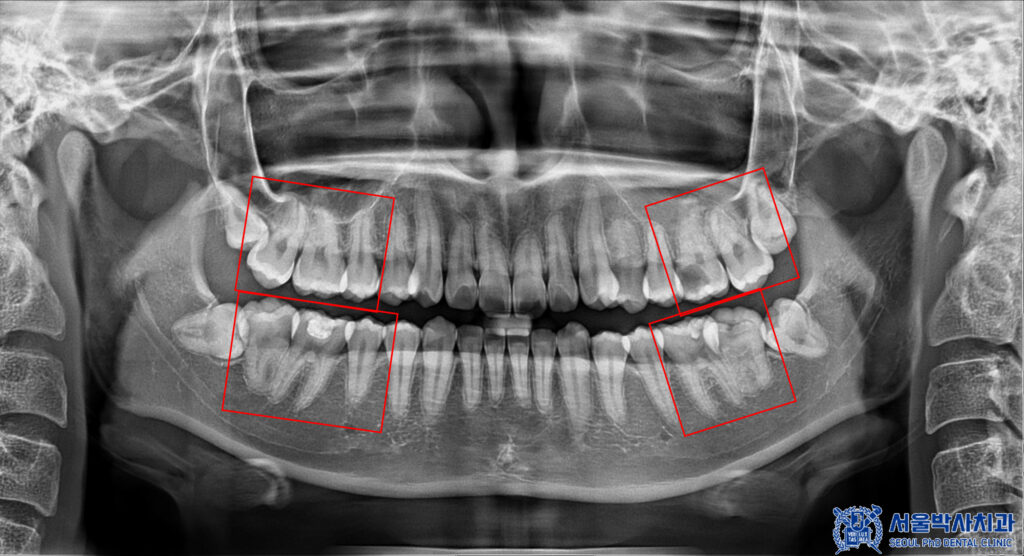

자세히 확인을 해보기 위해

파노라마를 촬영해 보았습니다.

파노라마 상에서도

다수 우식이 발견되었습니다.

신흥동치과 서울박사는

자연치아를 살리는 방향으로 진단하고

또 꼭 필요한 진료만 권해드리고자

충치가 깊지 않은 곳은 레진이나 인레이로,

충치가 깊은 곳은 신경치료 및 크라운으로

자연치아 보존 방향으로 치료를 계획하였습니다.